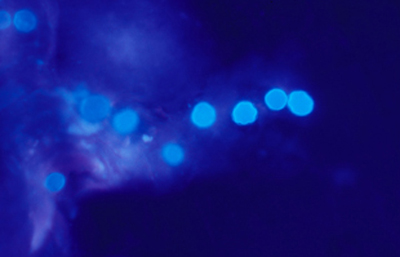

Blanco de Calcofluor

El uso del fluorocromo Blanco de Calcofluor no es excluyente de otras coloraciones, pues al ser en base acuosa no es permanente y la preparación puede lavarse en agua corriente para luego ser coloreadas con Giemsa, PAS u otras coloraciones, con el fin de reconfirmar los hallazgos microscópicos y volverlas permanentes para guardarlas.

Blanco de Calcofluor: Sobre el porta-objetos con el extendido ya fijado colocar unas gotas de Blanco de Calcofluor al 0.1% y de Azul de Evans 0.1%. Esperar 3 minutos. Cubrirlo con un cubre-objetos. Retirar con papel de filtro el exceso de líquido que se exterioriza por los bordes del cubre-objetos. Examen en el microscópio de fluorescencia. Emplear filtro excitador de 365 nm. y de emisión de 450-490 nm. Algunos autores favorecen emplear un filtro de emisión con longitud de onda más larga, fuera de la banda azul, en 520-550 nm. si bien con estas longitudes de onda la visualización de la emisión fluorescente es menos intensa.

Las imágenes de Acanthamoebas muestran una cápsula circular u ondulada, refringente de color azulado o verde manzana, notablemente más intensa que los materiales y tejidos que la rodean. Suelen medir de 12 a 16 µm de diámetro. El contenido del quiste es azul tenue. (Figura 37 , 38, 39 y 40)

Fig. 37 Blanco de Calcofluor (CW). Original x160

Fig. 38 CW, Original x250

Fig. 39 CW, Original x160

Fig. 40 CW, Original x160